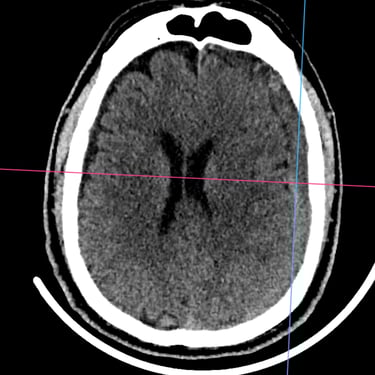

El hematoma subdural subagudo se caracteriza por la acumulación progresiva de sangre entre la duramadre y la superficie cerebral, generalmente posterior a un traumatismo craneal. Esta condición puede generar síntomas como dolor de cabeza persistente, confusión, debilidad en extremidades o alteración del estado de conciencia. El tratamiento quirúrgico consiste en la evacuación del hematoma mediante burr hole ampliado, técnica que permite realizar un orificio en el cráneo para drenar el contenido hemático y descomprimir el cerebro. Este procedimiento ayuda a disminuir la presión intracraneal, mejorar los síntomas neurológicos y prevenir complicaciones asociadas a la compresión cerebral.